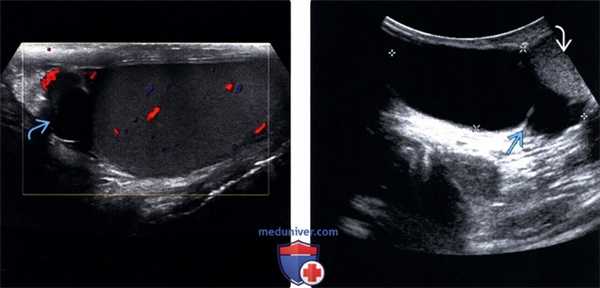

(Слева) Типичные признаки случайно обнаруженной и клинически незначимой кисты придатка яичка. Анэхогенный бессосудистый очаг с нечетким контуром в головке придатка яичка.

(Справа) В правой половине мошонки визуализируется крупная киста придатка яичка (отмечена калиперами) с единичной тонкой перегородкой, смещающая яичко книзу. Обратите внимание, что для выявления этого крупного очага потребовался не высокочастотный линейный датчик, а не абдоминальный датчик.

(Слева) Крупное сперматоцеле кверху от правого яичка, содержащее точечный низкоинтенсивный эхосигнал с артефактами на соответствующей допплерографии. В режиме реального времени эти точечные очаги были подвижны.

(Справа) УЗИ в продольной плоскости, В-режим: визуализируется сложное кистозное образование с многочисленными камерами с наличием взвеси, что является характерными признаками сперматоцеле.